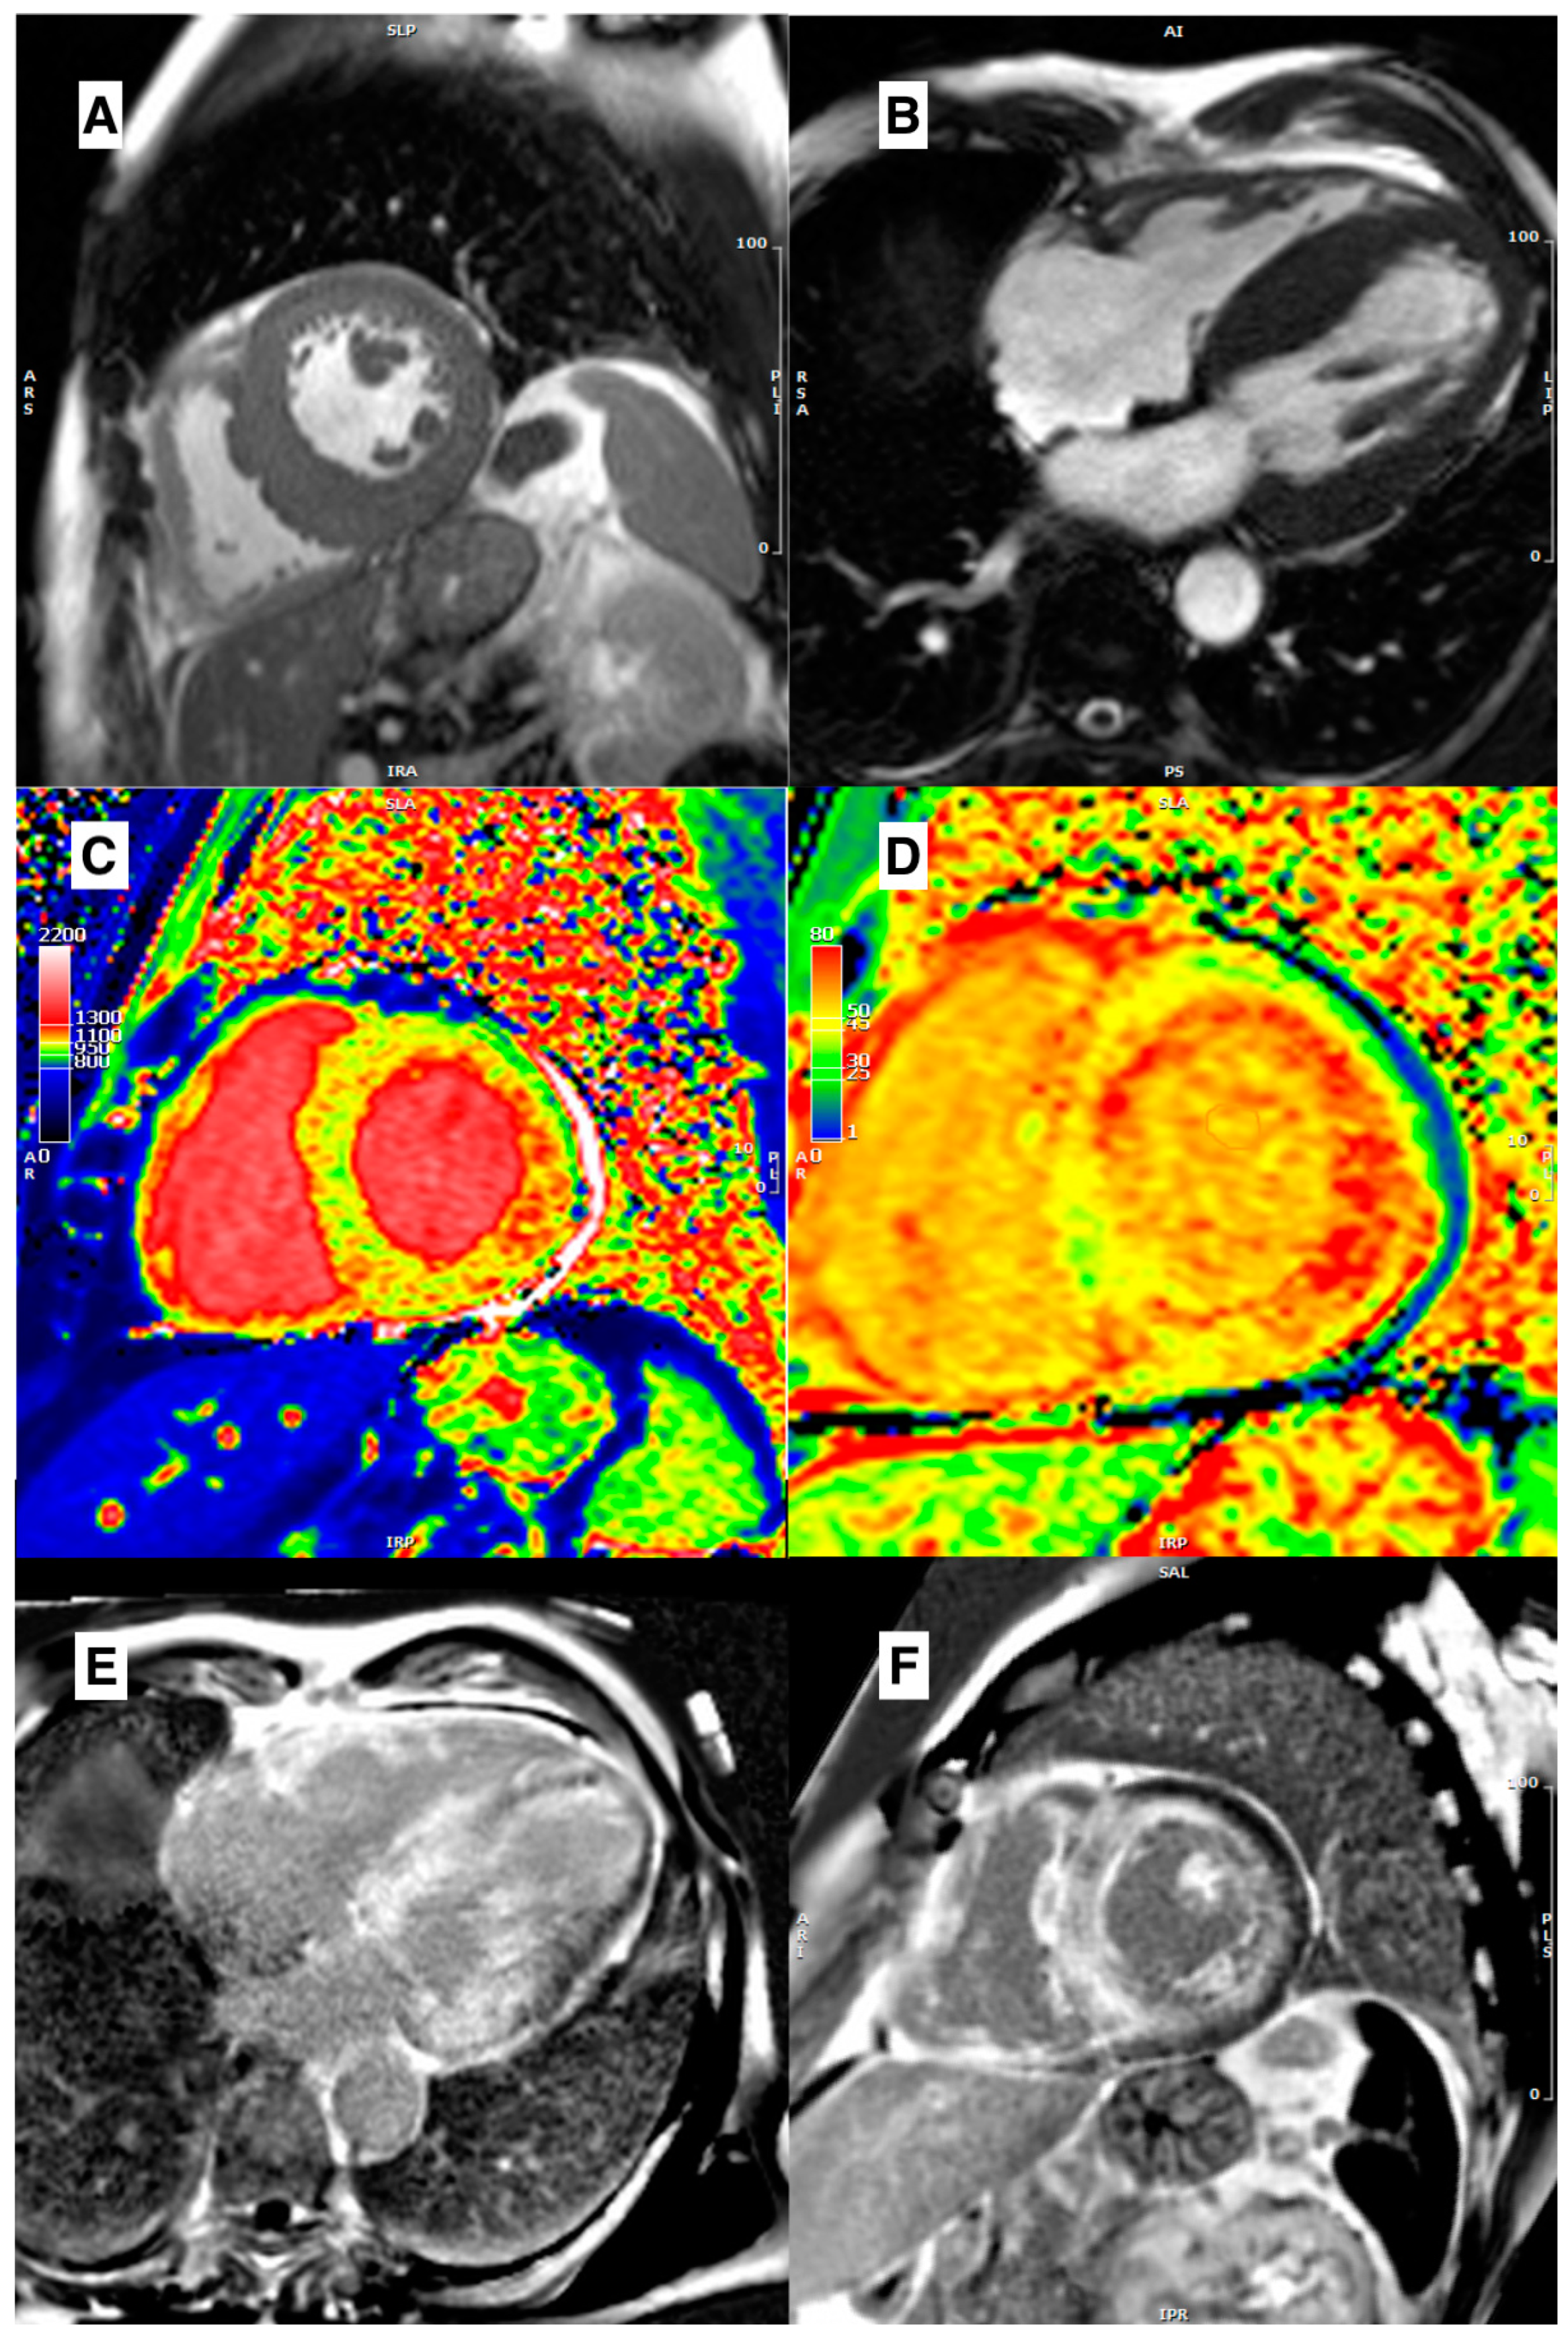

3.4. Role of Parametric Mapping

- Ferreira, V.M.; Piechnik, S.K. CMR Parametric Mapping as a Tool for Myocardial Tissue Characterization. Korean Circ. J. 2020, 50, 658–676. [Google Scholar] [CrossRef]

- Karamitsos, T.D.; Arvanitaki, A.; Karvounis, H.; Neubauer, S.; Ferreira, V.M. Myocardial Tissue Characterization and Fibrosis by Imaging. JACC Cardiovasc. Imaging 2020, 13, 1221–1234. [Google Scholar] [CrossRef]

- Messroghli, D.R.; Moon, J.C.; Ferreira, V.M.; Grosse-Wortmann, L.; He, T.; Kellman, P.; Mascherbauer, J.; Nezafat, R.; Salerno, M.; Schelbert, E.B.; et al. Clinical recommendations for cardiovascular magnetic resonance mapping of T1, T2, T2* and extracellular volume: A consensus statement by the Society for Cardiovascular Magnetic Resonance (SCMR) endorsed by the European Association for Cardiovascular Imaging (EACVI). J. Cardiovasc. Magn. Reson. 2017, 19, 75. [Google Scholar] [CrossRef] [PubMed]

- Dass, S.; Suttie, J.J.; Piechnik, S.K.; Ferreira, V.M.; Holloway, C.J.; Banerjee, R.; Mahmod, M.; Cochlin, L.; Karamitsos, T.D.; Robson, M.D.; et al. Myocardial Tissue Characterization Using Magnetic Resonance Noncontrast T1 Mapping in Hypertrophic and Dilated Cardiomyopathy. Circ. Cardiovasc. Imaging 2012, 5, 726–733. [Google Scholar] [CrossRef] [PubMed]

- Kato, S.; Nakamori, S.; Bellm, S.; Jang, J.; Basha, T.; Maron, M.; Manning, W.J.; Nezafat, R. Myocardial Native T1 Time in Patients With Hypertrophic Cardiomyopathy. Am. J. Cardiol. 2016, 118, 1057–1062. [Google Scholar] [CrossRef]

- Huang, L.; Ran, L.; Zhao, P.; Tang, D.; Han, R.; Ai, T.; Xia, L.; Tao, Q. MRI native T1 and T2 mapping of myocardial segments in hypertrophic cardiomyopathy: Tissue remodeling manifested prior to structure changes. Br. J. Radiol. 2019, 92, 20190634. [Google Scholar] [CrossRef]

- Amano, Y.; Yanagisawa, F.; Tachi, M.; Hashimoto, H.; Imai, S.; Kumita, S. Myocardial T2 Mapping in Patients With Hypertrophic Cardiomyopathy. J. Comput. Assist. Tomogr. 2017, 41, 344–348. [Google Scholar] [CrossRef]

- Arcari, L.; Hinojar, R.; Engel, J.; Freiwald, T.; Platschek, S.; Zainal, H.; Zhou, H.; Vasquez, M.; Keller, T.; Rolf, A.; et al. Native T1 and T2 provide distinctive signatures in hypertrophic cardiac conditions—Comparison of uremic, hypertensive and hypertrophic cardiomyopathy. Int. J. Cardiol. 2020, 306, 102–108. [Google Scholar] [CrossRef] [PubMed]

- Sado, D.M.; Flett, A.S.; Banypersad, S.M.; White, S.K.; Maestrini, V.; Quarta, G.; Lachmann, R.; Murphy, E.; Mehta, A.; Hughes, D.; et al. Cardiovascular magnetic resonance measurement of myocardial extracellular volume in health and disease. Heart 2012, 98, 1436–1441. [Google Scholar] [CrossRef] [PubMed]

- Swoboda, P.P.; McDiarmid, A.K.; Erhayiem, B.; Broadbent, D.A.; Dobson, L.E.; Garg, P.; Ferguson, C.; Page, S.P.; Greenwood, J.P.; Plein, S. Assessing Myocardial Extracellular Volume by T1 Mapping to Distinguish Hypertrophic Cardiomyopathy From Athlete’s Heart. J. Am. Coll. Cardiol. 2016, 67, 2189–2190. [Google Scholar] [CrossRef]

- Karamitsos, T.D.; Piechnik, S.K.; Banypersad, S.M.; Fontana, M.; Ntusi, N.B.; Ferreira, V.M.; Whelan, C.J.; Myerson, S.G.; Robson, M.D.; Hawkins, P.N.; et al. Noncontrast T1 Mapping for the Diagnosis of Cardiac Amyloidosis. JACC Cardiovasc. Imaging 2013, 6, 488–497. [Google Scholar] [CrossRef] [PubMed]

- Fontana, M.; Banypersad, S.M.; Treibel, T.A.; Maestrini, V.; Sado, D.M.; White, S.K.; Pica, S.; Castelletti, S.; Piechnik, S.K.; Robson, M.D.; et al. Native T1 Mapping in Transthyretin Amyloidosis. JACC Cardiovasc. Imaging 2014, 7, 157–165. [Google Scholar] [CrossRef]

- Baggiano, A.; Boldrini, M.; Martinez-Naharro, A.; Kotecha, T.; Petrie, A.; Rezk, T.; Gritti, M.; Quarta, C.; Knight, D.S.; Wechalekar, A.D.; et al. Noncontrast Magnetic Resonance for the Diagnosis of Cardiac Amyloidosis. JACC Cardiovasc. Imaging 2020, 13, 69–80. [Google Scholar] [CrossRef] [PubMed]

- Kotecha, T.; Martinez-Naharro, A.; Treibel, T.A.; Francis, R.; Nordin, S.; Abdel-Gadir, A.; Knight, D.S.; Zumbo, G.; Rosmini, S.; Maestrini, V.; et al. Myocardial Edema and Prognosis in Amyloidosis. J. Am. Coll. Cardiol. 2018, 71, 2919–2931. [Google Scholar] [CrossRef]

- Sado, D.M.; White, S.K.; Piechnik, S.K.; Banypersad, S.M.; Treibel, T.; Captur, G.; Fontana, M.; Maestrini, V.; Flett, A.S.; Robson, M.D.; et al. Identification and Assessment of Anderson-Fabry Disease by Cardiovascular Magnetic Resonance Noncontrast Myocardial T1 Mapping. Circ. Cardiovasc. Imaging 2013, 6, 392–398. [Google Scholar] [CrossRef] [PubMed]

- Thompson, R.B.; Chow, K.; Khan, A.; Chan, A.; Shanks, M.; Paterson, I.; Oudit, G.Y. T 1 Mapping With Cardiovascular MRI Is Highly Sensitive for Fabry Disease Independent of Hypertrophy and Sex. Circ. Cardiovasc. Imaging 2013, 6, 637–645. [Google Scholar] [CrossRef] [PubMed]

- Pica, S.; Sado, D.M.; Maestrini, V.; Fontana, M.; White, S.K.; Treibel, T.; Captur, G.; Anderson, S.; Piechnik, S.K.; Robson, M.D.; et al. Reproducibility of native myocardial T1 mapping in the assessment of Fabry disease and its role in early detection of cardiac involvement by cardiovascular magnetic resonance. J. Cardiovasc. Magn. Reson. 2014, 16, 99. [Google Scholar] [CrossRef]